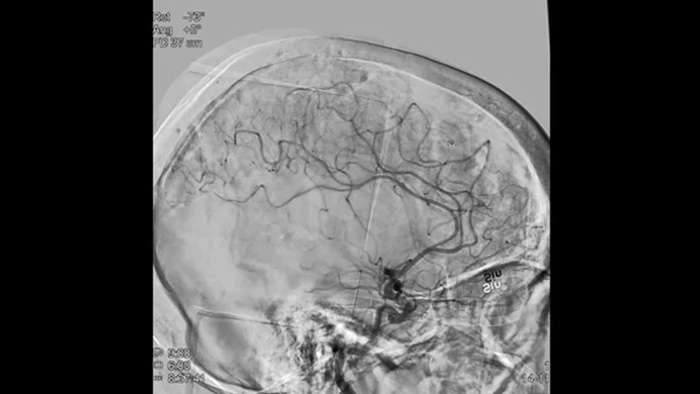

Images nettes avec ASN 2D avec technologie ClarityIQ

ASN 2D avec la technologie ClarityIQ

ClarityIQ applique la compensation automatique des mouvements lors de l’angiographie par soustraction numérique (ASN) en temps réel pour maintenir la netteté des images des vaisseaux et contribuer à une prise de décision fiable tout au long des procédures d’AVC.

Visualisation d’angiographie par soustraction numérique (ASN)

Les visualisations d’angiographie par soustraction numérique (ASN) de haute qualité vous permettent d’évaluer si vous avez retiré le caillot complet et si des morceaux de caillot ont été dispersés de manière distale dans le cerveau. Vous pouvez vérifier le rétablissement du débit sanguin dans la pénombre et contrôler les hémorragies péri-procédurales.